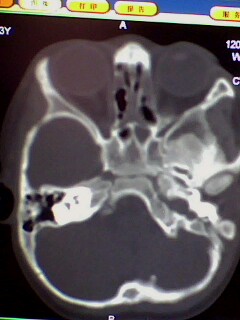

标题: PED3023:鼻咽增殖体肥大。

男,3岁小儿,经常睡觉时张口呼吸、打鼾。

1、左侧乳窦气房硬化型改变,是发育不完全还是鼻咽增殖体肥大阻塞咽鼓管开口引起中耳炎?

2、双上颌窦应该有炎症了吧,听好多人说,小孩副鼻窦还没发育完全也可有这种表现,究竟两者怎样鉴别?请各位战友指点。多谢

腺样体肥大,双侧上颌窦炎症,原因支持楼主。乳突体位不正,个人发育有差异,观察吧。

腺样体肥大,副鼻窦炎症。支持!乳突尚未发育完全,加上位置不标准不好说。